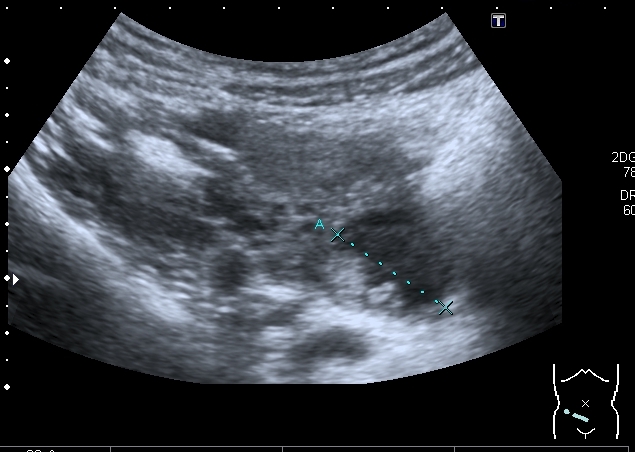

Сходные по структуре образования в левом яичнике